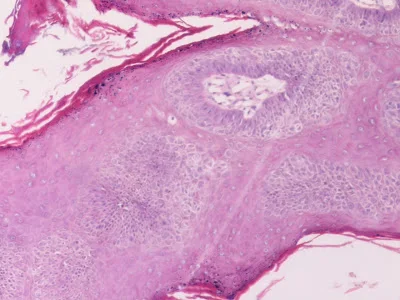

Genel Patoloji (Ders Notları)